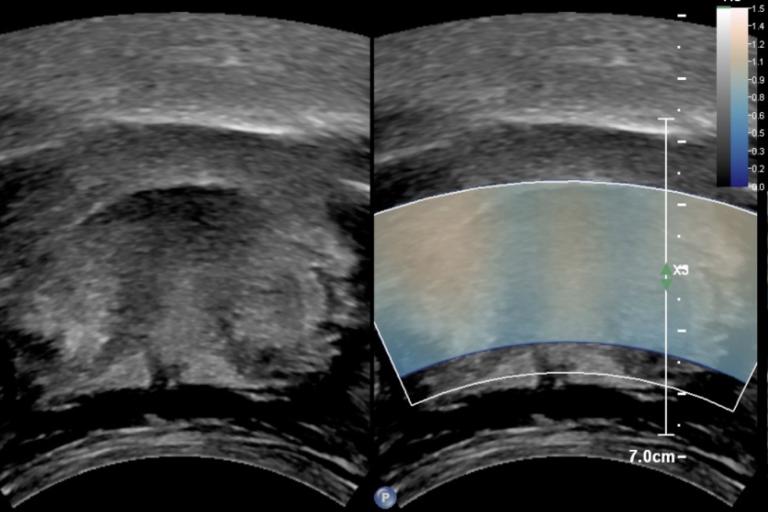

- Liver fat, inflammation, and fibrosis quantification in non-alcoholic fatty liver disease (NAFLD) and non-alcoholic steatohepatitis (NASH)

- Confounders of measurement consistency

- Use of shear wave elastography in novel applications of superficial ultrasound